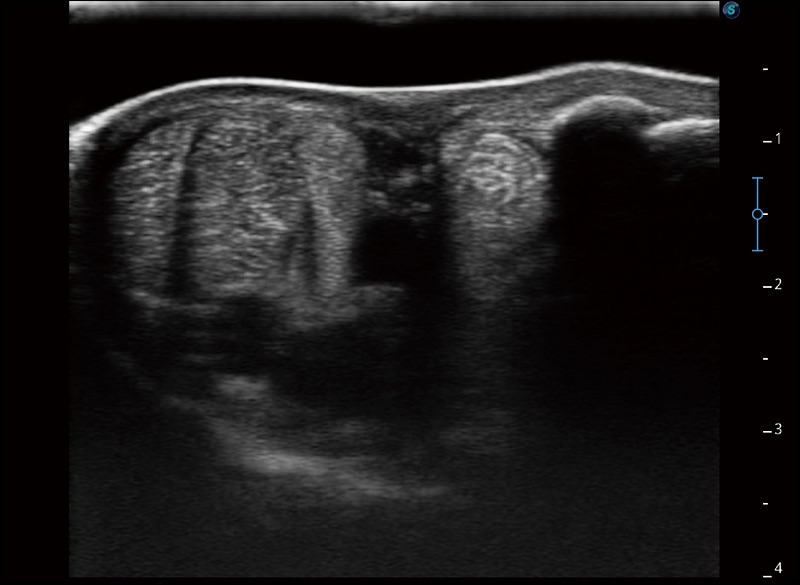

扩展成像

支持线阵和凸阵探头,一键操作即可获得更宽的图像视野

实时宽景成像

可实时观察感兴趣区域和病变位置

穿刺针增强

高清显示穿刺进针情况